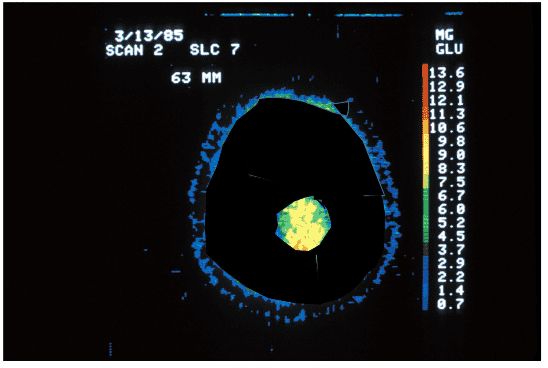

Ale takto PET sken v skutočnosti nevyzerá. Snímka nižšie zobrazuje skutočný sken zdravého človeka. Celý mozog je neustále aktívny, dokonca aj v obdobiach spánku: reguluje, monitoruje, sníma, interpretuje, usudzuje, plánuje a koná. Dokonca aj ľudia s degeneratívnymi nervovými poruchami, ako je Alzheimerova a Parkinsonova choroba, stále používajú viac ako 10% svojho mozgu.

psychologicalscience.org